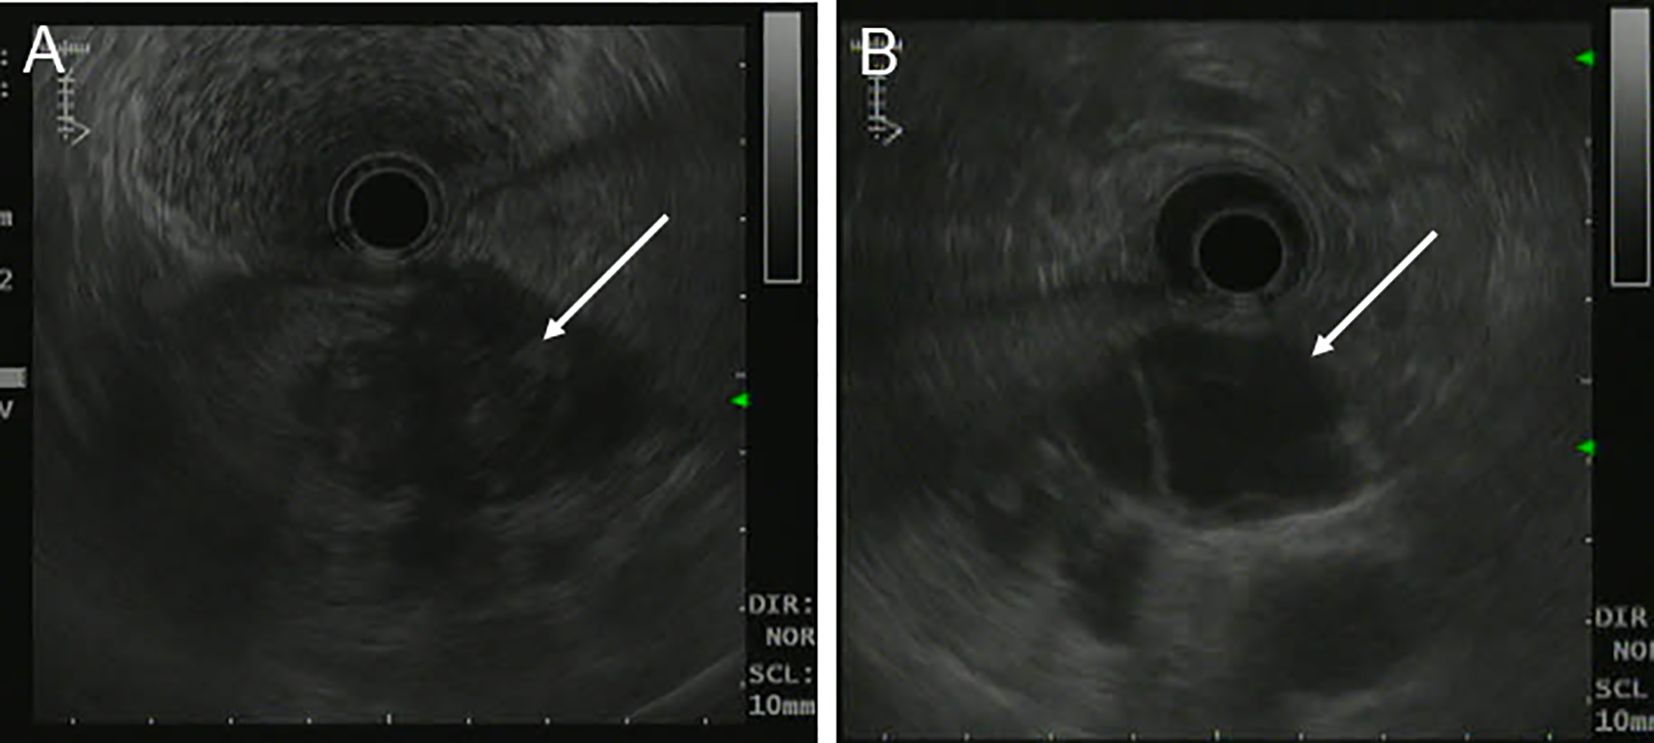

A 39-year-old woman presented with left upper abdominal pain for 20 days and was admitted to the hospital. The pain is persistent and dull in the epigastric region. She described the pain as dull, severe, and non-radiating. The pain was heavier at night than during the day and was related to body position. The bent-knee and bent-hip positions could reduce the pain. It was frequently accompanied by nausea and vomiting, and the vomit was gastric contents and bile. An abdominal CT scan and MRI performed at another hospital had revealed a space-occupying lesion in the pancreas. There was no relevant medical or family history, and the patient had no history of smoking or alcohol consumption. On physical examination, the patient presented with a good general condition and no abnormalities of note. Laboratory tests showed (reference ranges are given in square brackets) the following: glutamyl transferase (72 U/L, reference range 7–32 U/L); lipase (62 U/L, reference range <60 U/L); amylase (31 U/L, reference range 35–135 U/L); and alkaline phosphoric acid (234 U/L, reference range 45–125 U/L). The tumor marker showed no obvious abnormality (CEA, CA199, AFP, and CA125 are normal). The ultrasonography showed a mixed cystic-solid echogenic structure between the body of the pancreas and the posterior wall of the stomach (Figure 1). The mass size was approximately 5.9 cm × 4.1 cm × 3.2 cm with a well-defined margin. The mass was observed to be internally separated by multiple compartments, but there was no obvious relationship with the stomach. A small amount of blood flow signal could be seen. Endoscopic ultrasonography showed a large cystic solid mass in the gastric sinus, posterior to the gastric wall, and at the neck of the pancreas (Figure 2). It was approximately 5.2 × 3.4 cm in size; the border lacked clear boundaries; the solid area was predominant at the wall of the gastric antrum; and the gastric body was dominant behind the cystic region. Multiple septations could be seen within the lesion. The CT plain scan and enhancement showed a mass of flaky cystic-solid mixed-density shadows in the pancreas and gastric hiatus; the lesion was indistinctly distinguished from the gastric wall and the body of the pancreas, and it measured about 6.93 × 3.87 cm. Enhancement scan of the solid portion of the inhomogeneous enhancement, which was considered the possibility of a gastric mesenchymal tumor. MRI showed the lesion with slightly longer T1 and T2 signals, slightly higher signals on DWI, and slightly lower signals on ADC; mild-moderate enhancement; unclear borders; and approximately 3.6 cm × 3.6 cm × 2.8 cm in size; the lesion was poorly demarcated from the neck of the pancreas (Figure 3). To prevent iatrogenic tumor cell dissemination, we also considered the patient’s preference for surgery. Taking all these factors into consideration, we did not perform an endoscopic ultrasound.

Figure 2. Endoscopic Ultrasonography of patient before operation. (A, B) A large cystic-solid mass was observed at the junction of the posterior gastric antrum and pancreatic neck, with poorly defined borders and predominantly cystic components.